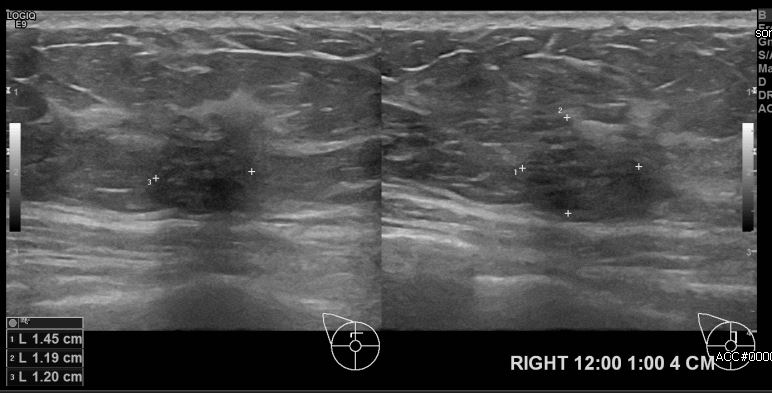

상기환자 건강검진상 이상소견으로 내원하신 40대 여성분으로 우측유방 12시에서 1시 방향에서 4cm 떨어진 거리의 의심스러운 멍울 조직검사 시행하여 우측 침윤성 유관암 진단 되었습니다.